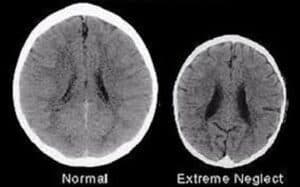

Too much stress, however, can be harmful to us especially if it is for a prolonged period of time. This is known as toxic stress. When experienced, the hypothalamic-pituitary and adrenal hormone axis are over-activated. Cortisol increases in the blood level which causes inflammation and compromised immunity. This can lead to permanent changes in the development of the brain, to the brain’s plasticity, and other organs that depend on outputs from the brain. As a result, stress can impact functioning and quality of life in the future, having mental and physical effects.

Toxic stress can significantly impede young people’s cognitive development. When prolonged adversity is present in a child’s environment it can have long-term effects including “developmental delays, compounded by additional problems including cardiovascular disease, diabetes, substance abuse, and depression throughout life.” (Kaboom)